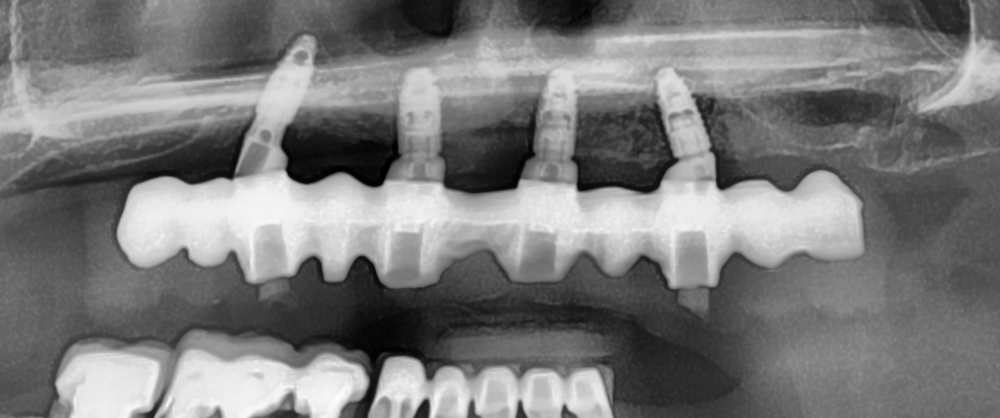

Reprise de traitement implantaire

La reprise de traitement désigne le processus par lequel un patient reprend des soins après un échec de traitement implantaire ou lorsque des complications surviennent. Voici les étapes typiques d’une reprise :

En cas d’échec ou de complications, la reprise de traitement implique une évaluation diagnostique, une extraction (si nécessaire), une cicatrisation, puis une reconstruction osseuse suivie d’une nouvelle implantation.